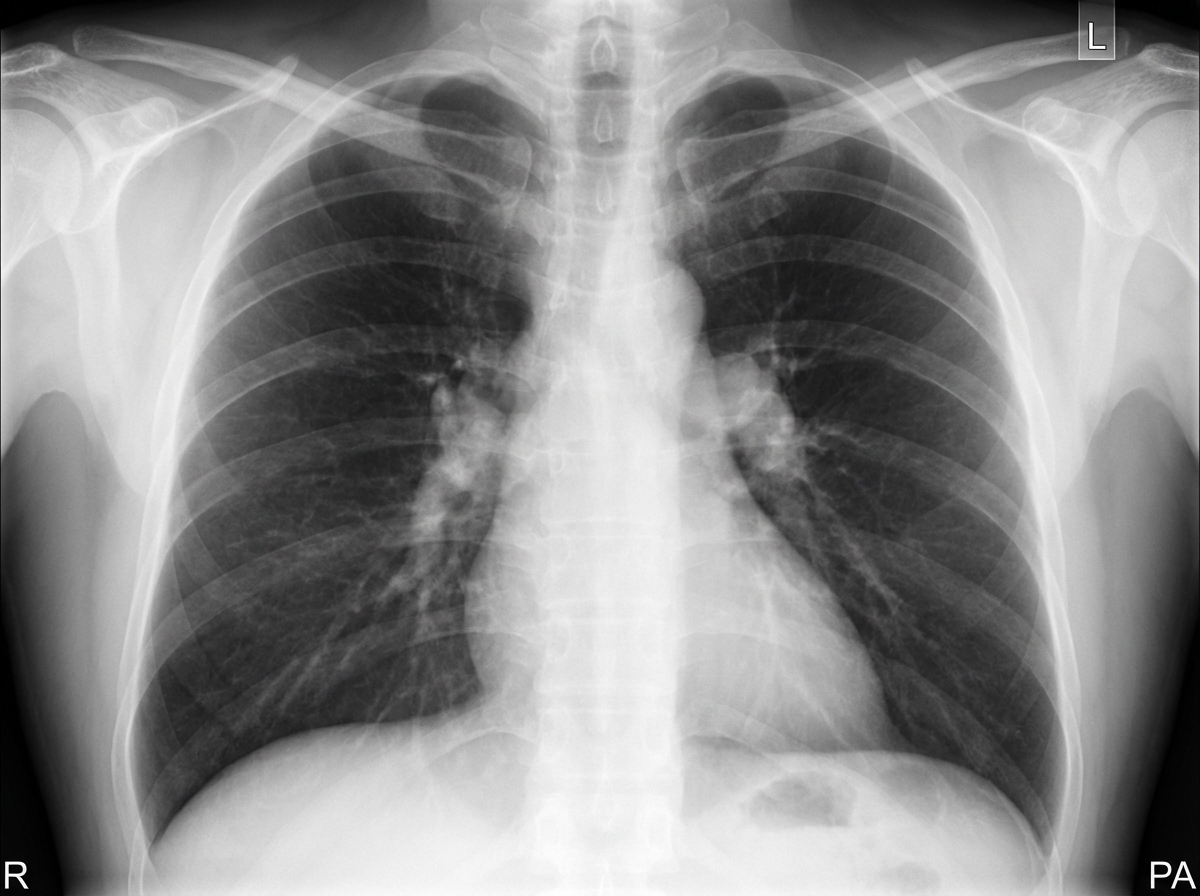

Explanation: ***Sarcoidosis*** - **Bilateral hilar lymphadenopathy** on chest X-ray is a classic finding in sarcoidosis, especially in young adults with respiratory symptoms. - Presents with **dry cough**, dyspnea, and systemic symptoms; often has **non-caseating granulomas** on biopsy. *Aspergillosis* - Typically causes **cavitary lesions** or **aspergilloma** formation on chest imaging, not bilateral hilar lymphadenopathy. - More common in **immunocompromised patients** or those with pre-existing lung disease like asthma or COPD. *Coccidioidomycosis* - Endemic to **southwestern United States** and presents with **unilateral hilar adenopathy** or pulmonary nodules. - Often associated with **travel history** to endemic areas and may cause **erythema nodosum** as extrapulmonary manifestation. *Granuloma annulare* - A **dermatologic condition** characterized by ring-shaped skin lesions, not a pulmonary disease. - Does not cause respiratory symptoms or **chest X-ray abnormalities**.